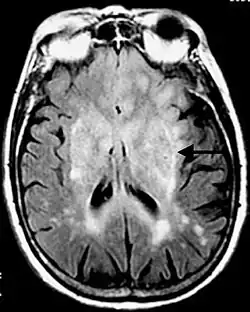

Secuencia FLAIR postcontraste de un caso de meningitis. Muestra la mejora de las meninges en el tentorio y en la región parietal, con evidencia de ventrículos dilatados.